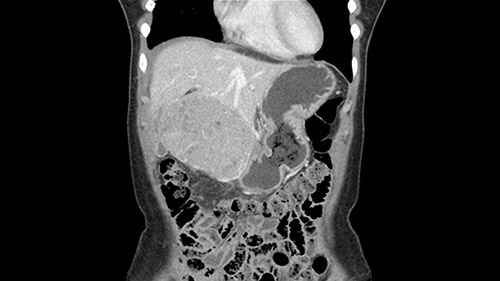

So if we look at the CT scan, on the axial, it’s a larger lesion. It’s about 6 or 7 or 8 centimeters. So it does look a bit threatening in terms of its resectability but if you really drill down deeply into the anatomy, and I think the coronal [imaging] is even better, you can see that the entire mass is on the patient’s left side of the falciform ligament. So it’s really only a left-sided tumor and not even really a left-sided tumor because Segment 4 is uninvolved anatomically.

When you see the axial sections of the scan, you find it's a largely exophytic mass and its well-encapsulated. So this is typically true of a well-differentiated hepatocellular carcinoma. If you look at this, this is the gallbladder which is being displaced to the right and the mass is in the Sg4 of the liver, exophytic, projecting down. As it is coming down, it is also displacing the duodenum and the head of the pancreas which is being pushed towards the left and it's going right up to the cava, the start of the anterior surface of the cava. Obviously getting a lot of collaterals and vascularity from all the vessels around but one has to be very careful in evaluation of the main portal pedicle in this particular case and of course arterial inflow to the Sg4 and of course the left lobe of the liver.

So in planning for this operation, as I look at the scans, I first visualize the arterial phase and I can see that there’s are a lot of big feeding arteries to this large tumor. Likely all the right side vessels feeding the right side of the liver: right hepatic artery and likely the Segment 4 artery are spared from the tumor. It’s likely the left hepatic artery is ramificating and giving feeding arteries to this tumor. It certainly looks like a large mass that its compressing other structures like the cava, the pancreas, the stomach; but I think there’s a plane and we can see that better in the venous phase. There’s a plane of separation between the gallbladder, the pancreas, the cava, that this tumor is abrupting but likely not invading. Usually, these masses actually don’t invade at that level and basically are pushing the tissues and once you open, you’re able to separate the tumor. Sometimes there’s some adhesions but you can actually separate and there’s usually no invasion.